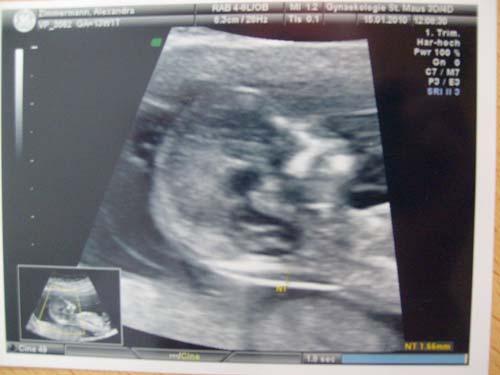

Heute war dann der 1. große Ultraschall. (wenn man den aus der 6. Woche mal weglässt) Bin zwar schon 14. Woche, aber eher ging halt nicht, mein Arzt war bis 6. Januar im Urlaub und danach hat es mti den Arbeitszeiten von meinem Mann nicht hingehaun. Ja also, erstmal das wichtige, das Baby ist super gut entwickelt, etwa 8 cm groß, alles normal, Hinterwandplazenta (juhu) und da ich ja nun zufällig 14. Woche war, hat er auch gleich mal die Nackenfalte mitgemessen, Baby lag gerade so günstig. 1,7 alles perfekt. Ja also Geschlecht..er hat mal drauf gehalten, weil ich ihn gefragt habe, und er meinte, also da könne er jetzt nicht mal ne Schätzung abgeben, es sah wie Schamlippen aus, aber er meinte das könnten zu so frühem Zeitpunkt auch genauso gut die Hoden sein. Also müssen wir warten bis zum nächsten Ultraschall um die 20. Woche rum. Ansonsten hat das Kind lebhaft rumgeturnt...was ja kein Wunder ist, blöde Ultraschallwellen :( aber zumindest war es fidel und man konnte das Herz, die Wirbelsäule, sogar das Nasenbein und ach alles sehen...ist schon echt wahnsinn was man heutzutage alles darstellen kann. Nachher noch Vorsorge bei meiner Hebamme *freu* Hier das obligatorische Bild...leider schlecht abfotografiert...haben leider keinen Scanner :(